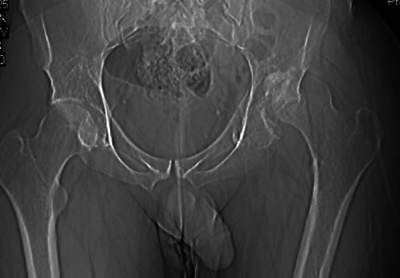

важаемые коллеги,пациент 23 лет (вес 75 кг), обратился к нам по поводу боли в тазобедренном суставе при ходьбе, нестабильность в нем при нагрузке. Ходит с тростью. 8 мес. назад попал в ДТП (никаких медицинских документов у него нет). Стоит ли открываться и вправлять вывих или сразу делать бесцементное тотальное эндопротезирование? С уважением, А. В. Вакуленко Клиника эндопротезирования суставов, г. ДонецкDear All, male patient 23 y.o., body weight 75 kg. Had RTA 8 months ago (medical records unavailable). Now has pain on motion in his left hip. On weight-bearing hip is unstable (patient use cane while walking). Keeping in mind his age, is it worth to perform open reduction? Or just do uncemented THR? Any comments are very welcome.

After 8 months, the hip will not easily come down into the acetabulum. It also appears to me that there is an impression fracture of the head of femur.

Здравствуйте. Позвольте поучаствовать в обсуждении. Поскольку пациент в течение 8 месяцев не получил адекватного лечения (видимо и по своей вине тоже), а также учитывая удовлетворительное состояние головки бедра(по данным КТ), есть смысл выполнить открытое вправление головки бедра с возможной фиксацией фрагмента заднего края пластиной. Далее начать восстановление функции сустава, дозированную нагрузку. Возможно молодой возраст пациента поможет ему отдалить время эндопротезирования. Желаю успехов.